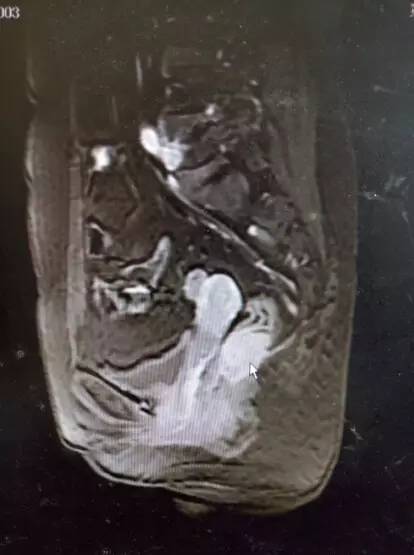

上腹部增强CT:1.肝右叶S6段占位,肿瘤性病变不除外2.肝脏小血管可能3.右肺下叶小空洞,建议进一步检查。(如图2)盆腔MRI:1.直肠中段管壁不规则增厚强化,考虑直肠癌可能大2.少量盆腔积液。(如图3)。

图3